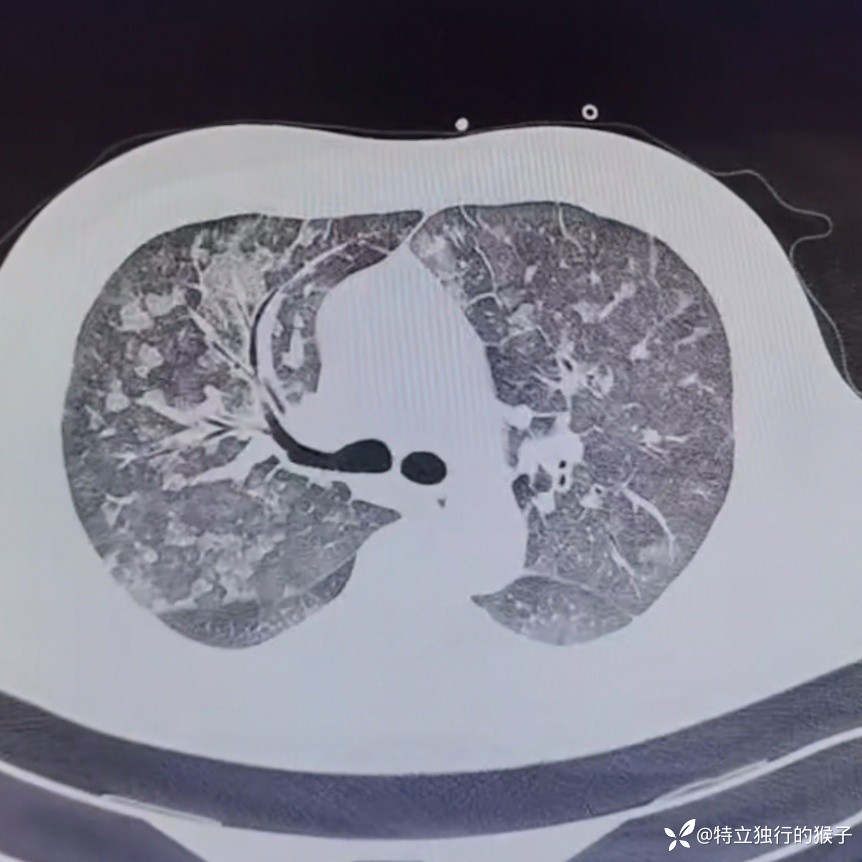

30y/M,1天前出现咳嗽,咳粉色泡沫痰,胸痛,胸闷气急,无发热。既往有肾炎病史。

查体:SpO2 85%,血压169/125mmHg,神志清,呼吸急促,口唇紫绀,两肺呼吸音粗,两肺闻及弥漫湿啰音,双下肢无水肿。

cTnI 0.66ng/ml;NT-proBNP 4183ng/ml。D-Dimer 0.17mg/l;肌酐271umol/L,BUN15mmol/L。